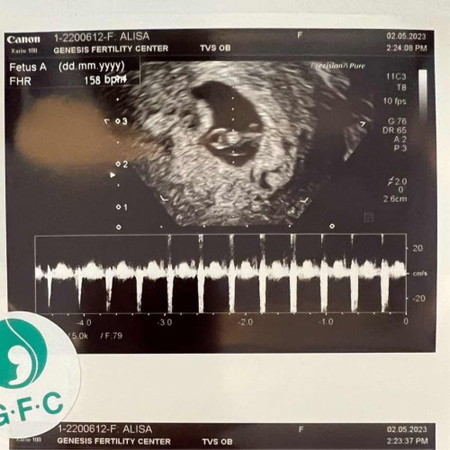

ได้กลับมาเป็นสมาชิกอีกครั้งหลังจากน้องหลุดไปเมื่อ 3 ปีที่แล้ว พยามเองจนท้อ เลยตัดสินใจทำ ICSI เมื่อปลายปีที่แล้ว ถึงบลาสต์ 8 ตัว ตรวจโครโมโซมผ่าน 2 ตัว (หญิง 1 ชาย 1) ย้ายลูกสาวมาก่อนเมื่อเดือนมี.ค. ตอนนี้มาอยู่ในพุงได้ 7 วีค 5 วันแล้วค่ะ ดีใจมากๆที่ได้เป็นแม่คนกับเค้าซะที รอมานาน ❤️